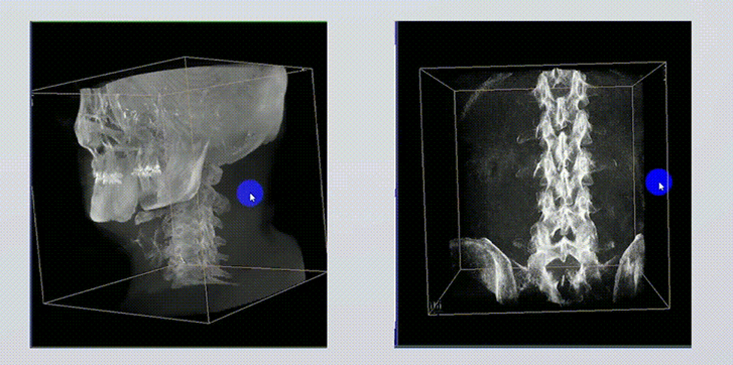

1、術(shù)中實時三維成像

術(shù)中三維成像和橫斷面圖像提供多角度的手術(shù)診斷信息,輔助醫(yī)生進行術(shù)中評估判斷,諸如骨折復(fù)位情況和內(nèi)植入螺釘?shù)某叽绾臀恢茫o助手術(shù)更好地完成。

2、三維成像視野大

提供更大的術(shù)中三維成像視野,采集更多圖像信息,可一次拍全全段頸椎、全段腰椎、七節(jié)胸椎、雙側(cè)骶髂關(guān)節(jié)、股骨頭及單側(cè)盆骨。